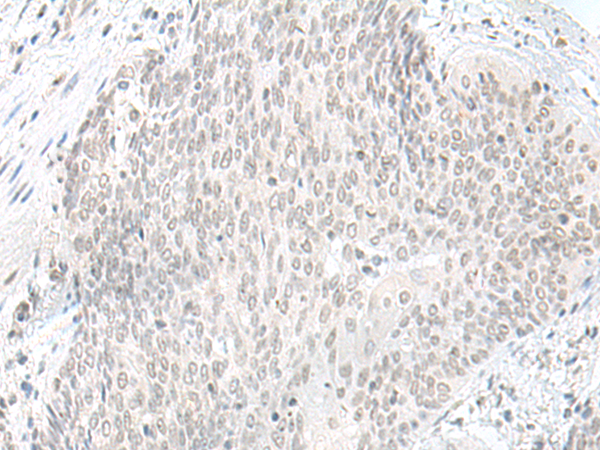

IHC positive control: |

Human esophagus cancer and Human liver cancer |

50-300 |